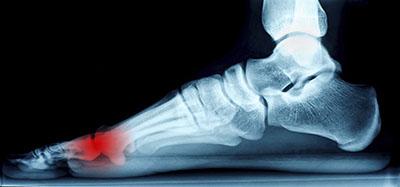

Conditions affecting the feet due to complications with arthritis can take many forms, including osteoarthritis, rheumatoid arthritis, gout, psoriatic arthritis, and ankylosing spondylitis. Osteoarthritis typically affects the joint connecting your big toe to your...

Ankle pain, while initially thought of as an issue for athletes, can affect anyone at anytime. Simple, everyday activities, such as walking or running on an uneven surface, have the possibility of causing serious harm to one’s ankle. That is, however, not to discount...

The Achilles tendon is not only the strongest, but also the largest tendon in the human body. The main function of the Achilles tendon is to transmit power from the calf muscles to the heel and the foot. It’s because of the Achilles tendon that we are able to stand on...

Morton’s neuroma may develop when the tissue around one of the nerves leading to your foot begins to thicken. When this occurs, you may experience some discomfort as if you were standing on a pebble stuck in your shoe. Most symptoms will not appear outwardly and will...